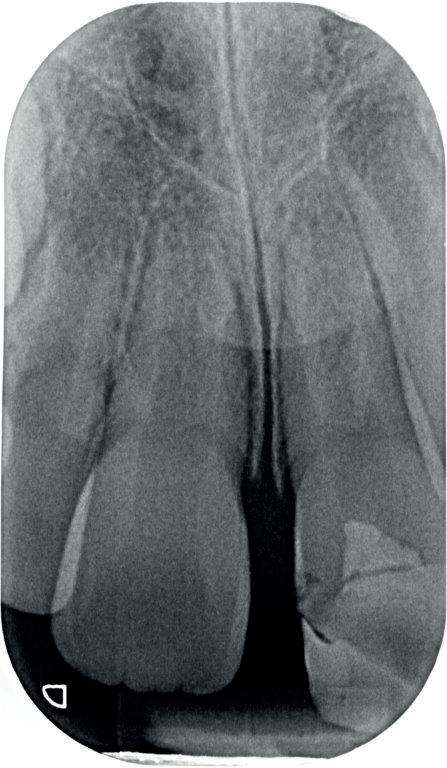

12. Röntgenbeeld 3 maanden na het trauma. Met dank aan Tristan Staas.

ENDODONTOLOGIE

gecontroleerd worden. Ook zullen er röntgenfoto’s worden gemaakt. Zolang er geen klachten en symptomen ontstaan, zal er een afwachtend beleid worden ingesteld. Uiteindelijk zal de radix van de 12 volledige worden vervangen voor bot. Hoelang dit duurt, is niet te voorspellen. Tegen die tijd, zal er overwogen worden om deze te vervangen door een implantaat met bijbehorende kroon.